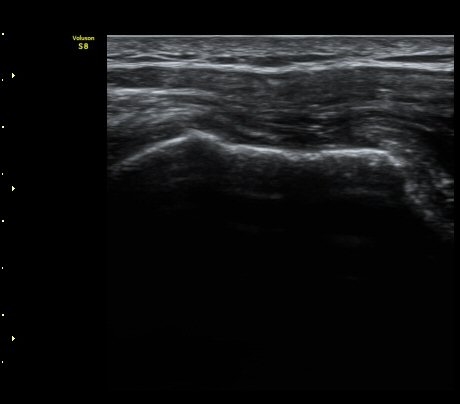

±Ø»ó°Ç Á¾´Ü¸é°Ë»ç¿¡¼­ ±Ø»ó°Ç ³»Ãø°ú ¿ÜÃø¿¡¼­ ÀüÃþÆÄ¿­ ¼Ò°ßÀ» º¸ÀÓ(½ÃÁø 1, 2).

°ß°©ÇÏ±Ù°Ç Á¾´Ü¸é°Ë»ç¿Í Ⱦ´Ü¸é°Ë»ç¿¡¼­ °ß°©ÇϱٰÇÀÇ ÀüÃþÆÄ¿­ ¼Ò°ßÀ» º¸ÀÓ(»çÁø 5, 6)